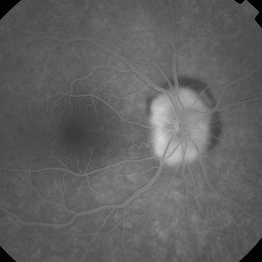

Aquired Vitelliform Maculopathy

Initial presentation.

Photographer: Wayne A Ladlee Jr

Imaging device: Cirrus

Condition/keywords: aquired vitelliform maculopathy